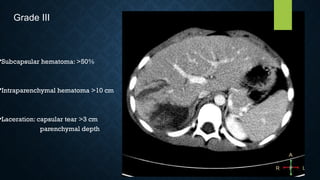

•Subcapsular hematoma: >50%

•Intraparenchymal hematoma >10 cm

•Laceration: capsular tear >3 cm

parenchymal depth

Grade III

•Subcapsular hematoma: >50% •Intraparenchymalhematoma >10 cm •Laceration: capsular tear >3 cm parenchymal depth Grade III